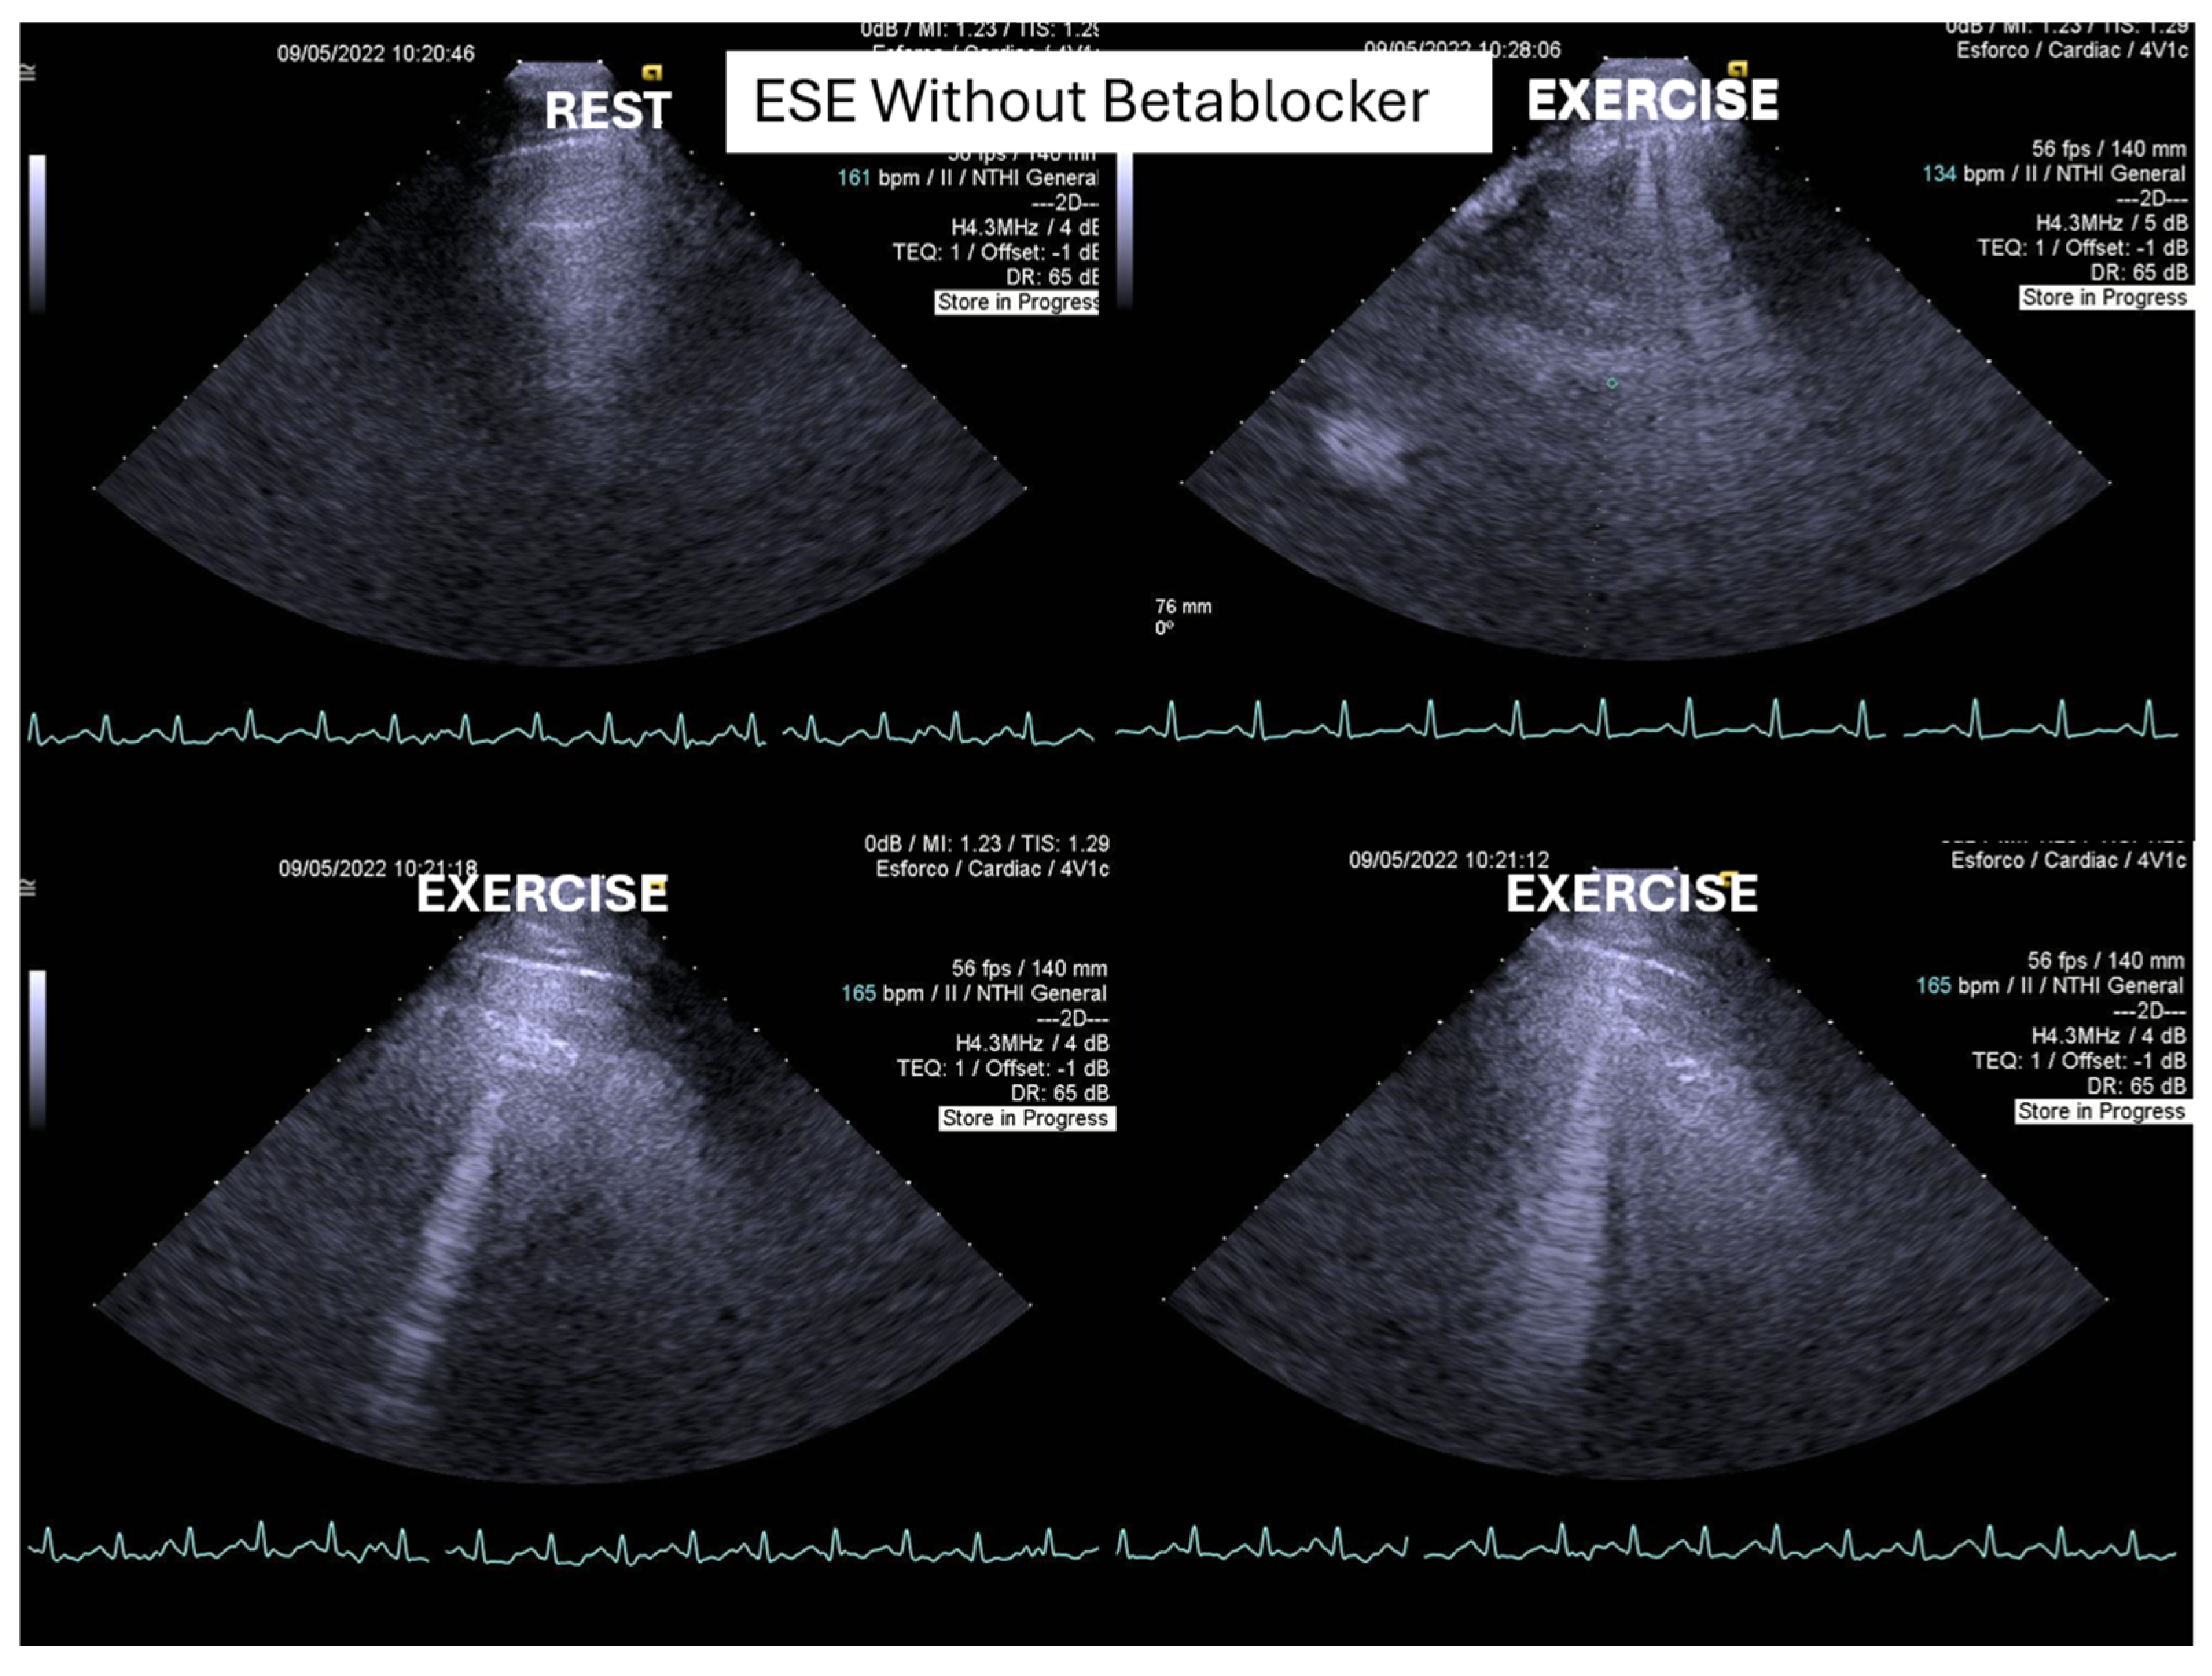

Of the 66 children enrolled in the study, 15 (23%) were female. The mean age was 14,6, 1,7 years old (11 to 17). On the resting echocardiogram, all the exams were considered normal with and without beta blockers. No wall motion abnormalities were detected in any of the exams, with or without beta blockers. IVPG (Figure 1) at peak exercise on the first assessment was 105 ± 38 mmHg, with mitral valve SAM in 28 children (Figure 2) in the complete group and 58 + 32 mmHg in only 29 children treated with beta-blockers, P< 0.0001.

Figure 1. This figure shows an intraventricular gradient during exercise in a child experiencing exercise-related chest pain and syncope, accompanied by elevated troponin levels (top). A significant reduction in the gradient is observed under beta-blocker therapy (bottom).

In our study, beta-blocker therapy was associated with a reduction in heart rate, exercise-induced ST-segment alterations, systolic blood pressure, and consequently, peak heart rate–systolic blood pressure product (HR×SBP). The incidence of intraventricular gradients (IVG) (Figure 1) and systolic anterior motion (SAM) of the mitral valve (Figure 2) during exertion also decreased significantly. These hemodynamic improvements were accompanied by a notable reduction in symptoms during exercise testing and follow-up (Figure 3 and Figure 4).

Figure 6. – IVPG at different stages of exercise in the same symptomatic children [5].